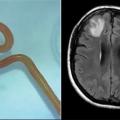

Ξεκινούν σύντομα οι πρώτες δοκιμές σε ανθρώπους

Η ασθενής υπέφερε από κατάθλιψη και προβλήματα μνήμης